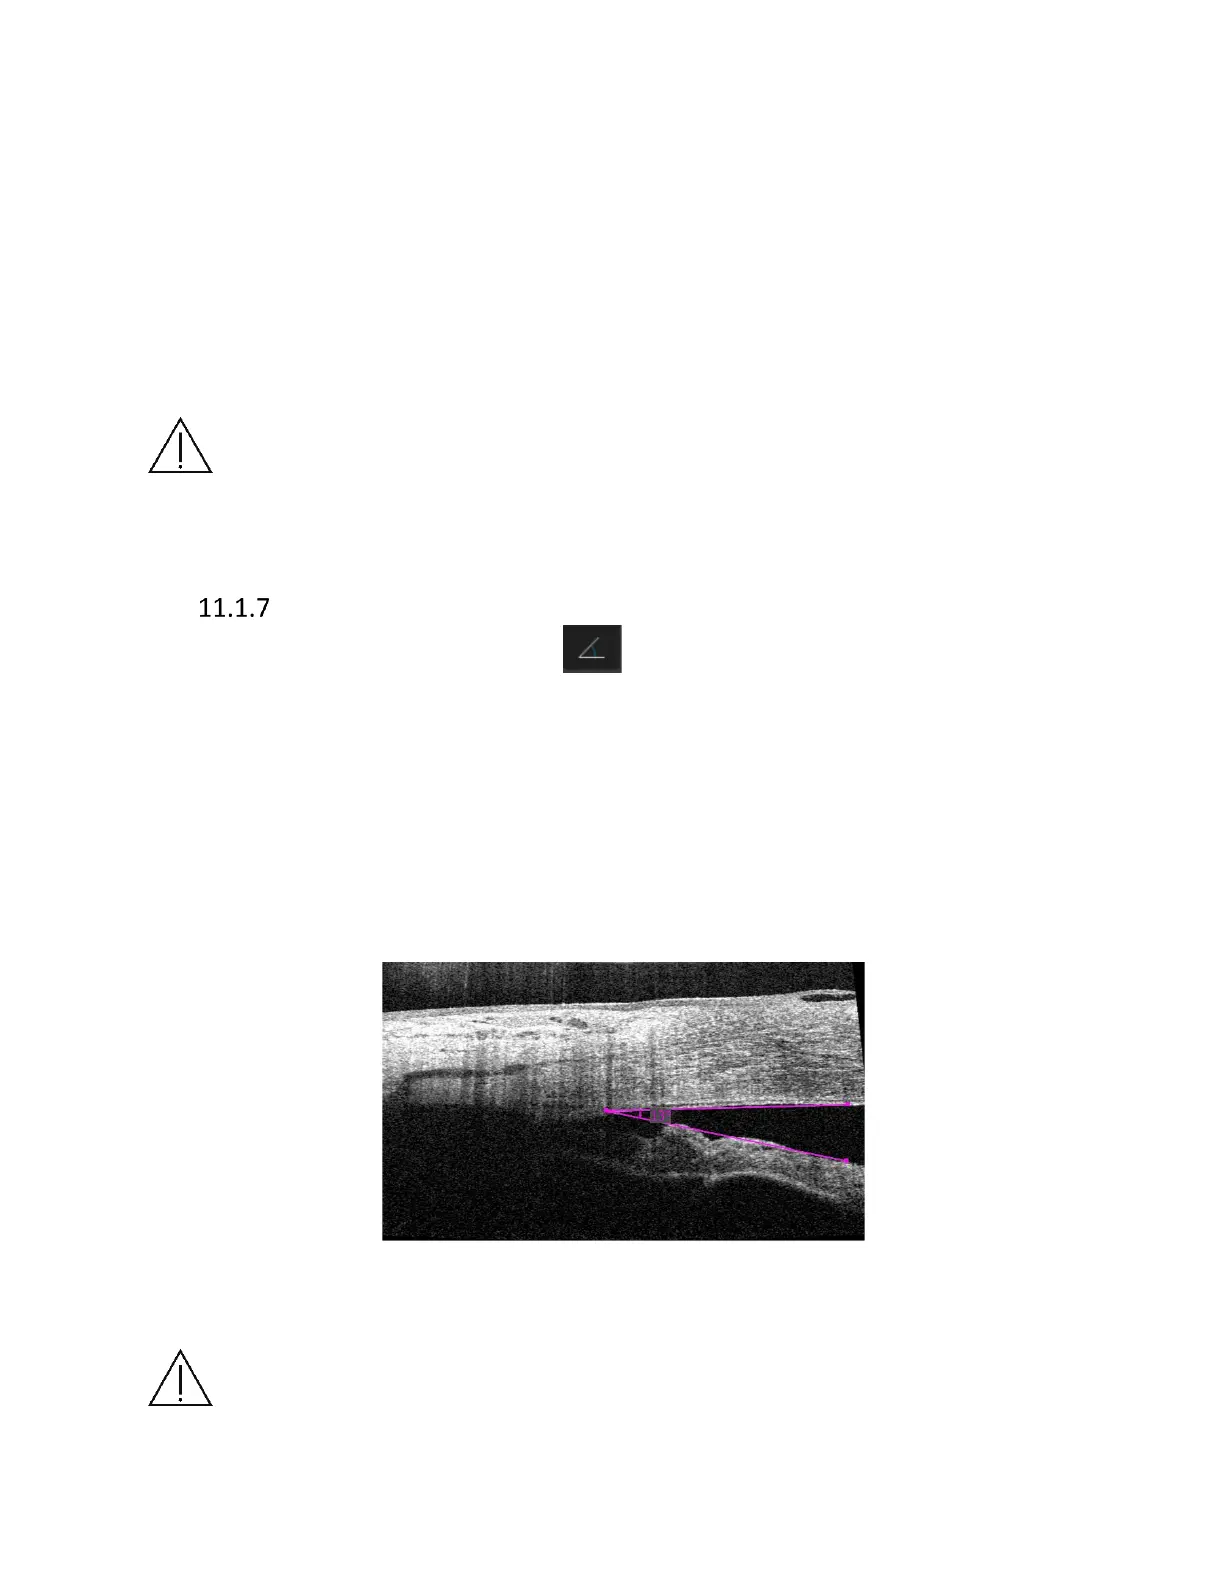

Angle measurement tool

This tool enables to measure an angle. Click Angle measurementbutton, put mouse cursor

over the place where you want the apex of the angle and click left-mouse button. Now click in the

place where you want to set one of the arms, place cursor of the angle to the desired position and

click for the second time. Information about angle will be displayed between the angle sides.

Measurements are expressed in degrees. It is also possible to move the position of the angle and

its measurement, by dragging and dropping its apex and the 2 points of measurement. The

measurement checkbox will affect also the angle visibility in the tomogram window, so select or

deselect this in order to show or hide the angle measurement.

Figure 143. Example of an angle measurement